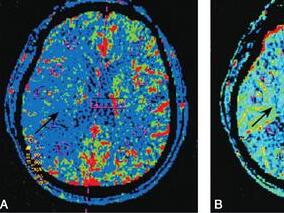

1小时条评论病例简介 例1 患者男,58岁,汉族。主因右上肢无力37日,加重伴意识障碍27日于2010年9月5日入我院。患者于入院前37日无明显诱因突发右上肢无力,伴言语不清,尚能行走,发病当日就诊于当地医院,发病初右侧上肢血压为200/100mmHg,行颅脑CT示左侧半卵圆中心腔隙性...